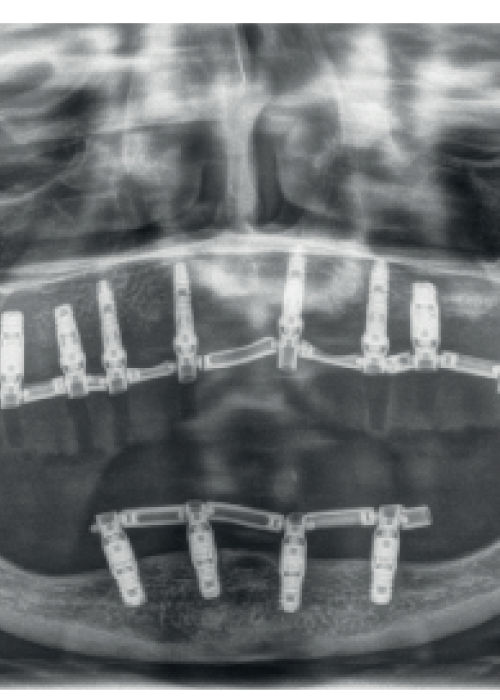

Injerto en bloque en combinación con la técnica de split en dos fases para la rehabilitación de un caso de gran reabsorción ósea del maxilar en anchura

Block grafting in combination with the two-stage split technique for the rehabilitation of a case of severe bone resorption of the maxilla in width